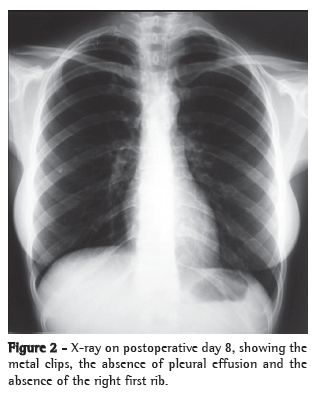

After the second intervention, the patient presented favorable evolution with a drastic decrease in chest drainage. On postoperative day 3, we introduced a diet with medium-chain triglycerides, although the diet was unrestricted from postoperative day 6 onward. On postoperative day 7, the chest tube was removed (Figure 2). The patient was discharged from the hospital on postoperative day 8, although still presenting difficulty in raising the right upper limb. After six months of follow-up treatment with an appropriate physical therapy program, the patient showed total recovery of the movements of the right upper limb. Pain and paresthesia ceased immediately after the surgery.